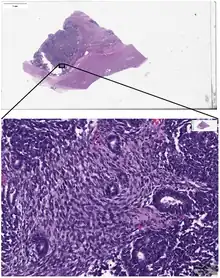

_stain_of_mixed_malignant_germ_cell_tumor_-_crop.png.webp)

Digital pathology has been approved by the FDA for primary diagnosis.[9] The approval was based on a multi-center study of 1,992 cases in which whole-slide imaging (WSI) was shown to be non-inferior to microscopy across a wide range of surgical pathology specimens, sample types and stains.[10] While there are advantages to WSI when creating digital data from glass slides, when it comes to real-time telepathology applications, WSI is not a strong choice for discussion and collaboration between multiple remote pathologists.[11] Furthermore, unlike digital radiology where the elimination of film made return on investment (ROI) clear, the ROI on digital pathology equipment is less obvious. The strongest ROI justification includes improved quality of healthcare, increased efficiency for pathologists, and reduced costs in handling glass slides.[12]